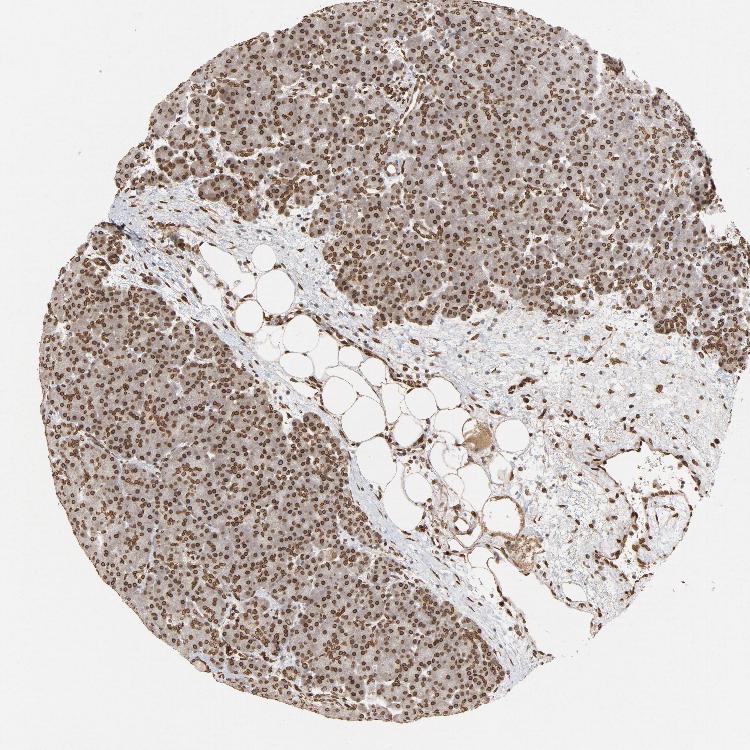

PANCREAS - Antibody stainingi

Antibody staining in the annotated cell types in the current human tissue is reported as not detected, low, medium, or high, based on conventional immunohistochemistry profiling in selected tissues. This score is based on the combination of the staining intensity and fraction of stained cells.

Each image is clickable and will lead to virtual microscopy that enables deeper exploration of all samples and also displays staining intensity scores, fraction scores and subcellular localization as well as patient and tissue information for each sample.

Antibody HPA006660Antibody CAB004022

Exocrine glandular cells HighHigh

Pancreatic endocrine cells MediumHigh